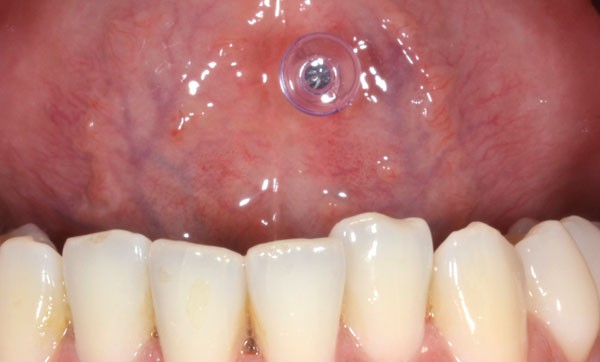

Les altérations de la surface dentaires sont plus fréquemment retrouvées avec les piercings linguaux qu’avec les piercings labiaux [3]. Ces défauts pourront être plus ou moins importants.

• Abrasion : le piercing constitue un élément exogène qui peut conduire à des pertes de substance dentaire par frottements mécaniques [2, 3] (fig. 2).

• Fêlures : elles apparaissent lorsque la taille du bijou n’est pas adaptée ou que celui-ci est trop long. Ces fêlures sont le résultat de chocs répétés du piercing sur les surfaces dentaires [4].